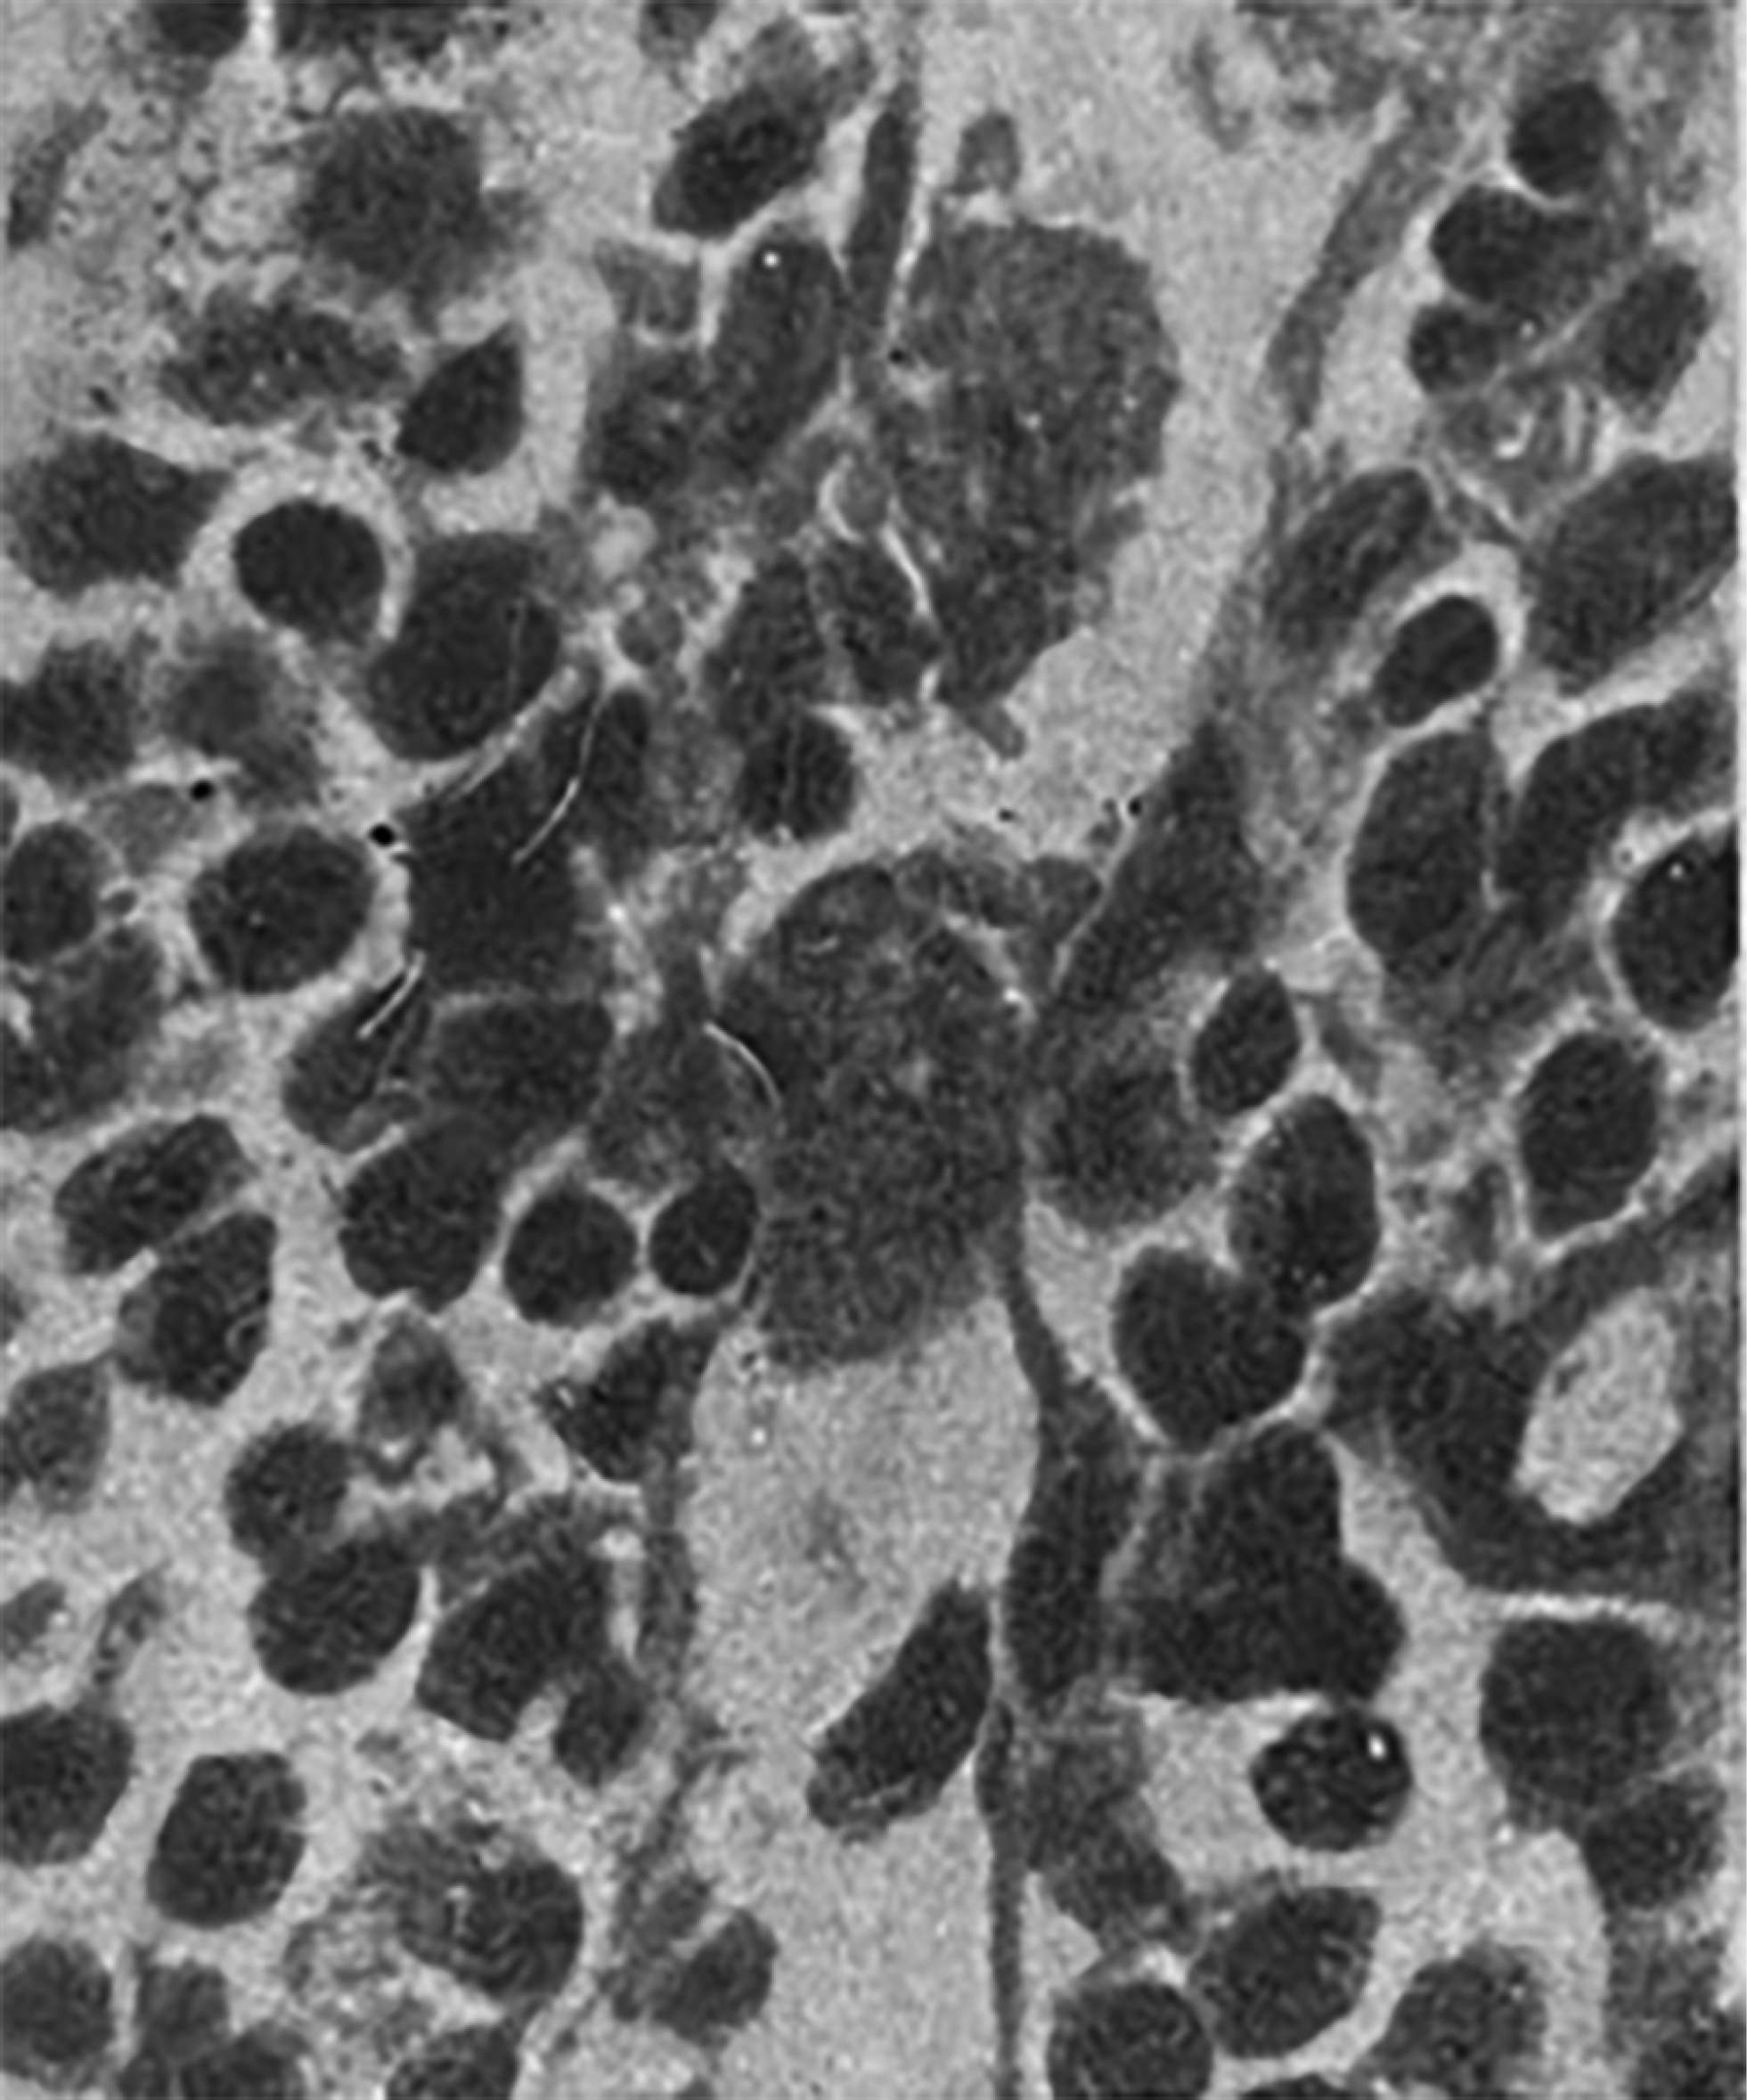

Яков Львович Рапопорт предложил морфологическую систематизацию различных форм контрактурных сокращений мышечных пучков миокарда и изучил патологическую анатомию острой сердечной недостаточности [6]. Контрактурная дистрофия в рамках главы об острой сердечной недостаточности вследствие применения аппарата искусственного кровообращения рассматривается им как морфологический субстрат острой сердечной недостаточности (см. рис. 4). Статья Я.Л. Рапопорта и Ю.Г. Тинякова расширила представление об этом состоянии, разделяя некоторые морфологические понятия: в частности, авторы разделили собственно контрактуры, полосы сокращения, фрагментации и зернисто-глыбчатый распад [7].

Яков Львович Рапопорт также принимал участие в изучении морфологической реакции ЦНС, гематоэнцефалического барьера на гипоперфузию в ходе операций с использованием аппарата искусственного кровообращения (рис. 5).

Рис. 5. Нейронофагия при острой гипоксии мозга [6].

Fig. 5. Neuronophagia in acute cerebral hypoxia [6].

Особое внимание Я.Л. Рапопорт уделял морфологической основе механизмов нервной и гуморальной регуляции иммуногенеза. Он подчёркивал особую значимость изучения роли лимфатического аппарата и ретикуло-гистиоцитарной системы (в терминах тех лет) как центра продукции антител. Им получены уникальные гистологические препараты тканей экспериментальных животных, сенсибилизированных экзогенными антителами (рис. 6) [6].

Рис. 6. Лимфатический узел морской свинки на 20-й день после введения дифтерийного анатоксина. Резкое набухание синусовых клеток, ретикулогистиоцитарная гиперплазия плазмоцитов [8].

Fig. 6. Lymph node of a guinea pig on the 20th day after administration of diphtheria toxoid. Sharp swelling of sinus cells, reticulohistiocytic hyperplasia of plasma cells [8].